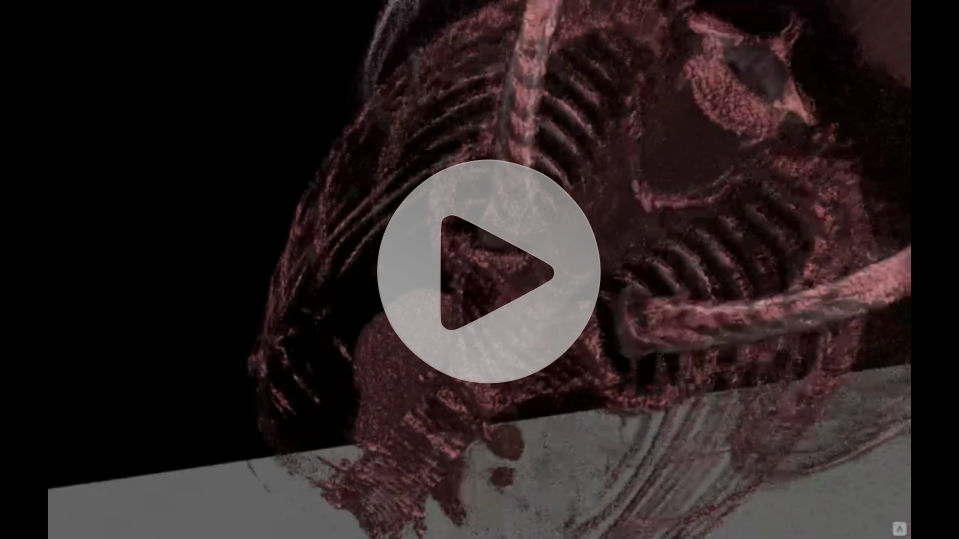

Preview of CT images from

brand new perspective

A modern program for analizing images from the tomograph

Thanks to our program, you will be able to manage lists of your patients in a quick and organized manner, saving time and more efficiently analyzing images from a computer tomograph or magnetic resonance imaging. The application allows you to load photos into the Virtual Reality environment, giving you the opportunity to view and analyze them in a new, unconventional way. Photos displayed in the form of 3D models can be freely rotated and viewed from different angles.